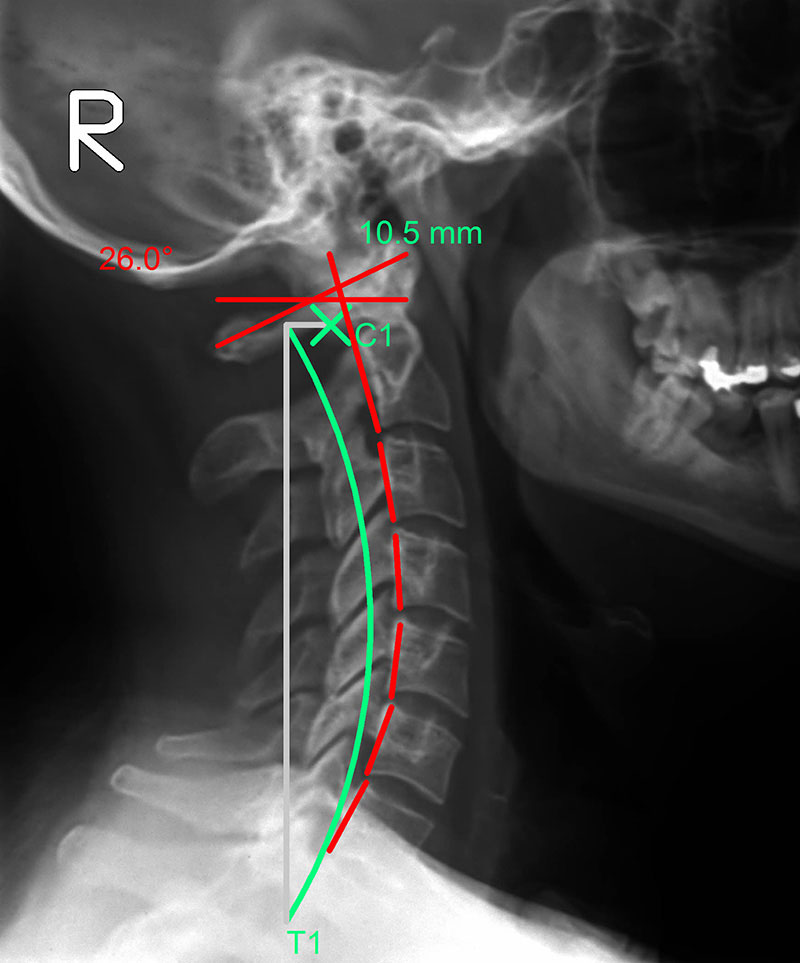

Une lordose cervicale (du cou) saine

Cyphose

Un renversement de la courbure

cervicale pouvant mener à

des problèmes de santé sérieux

La ligne verte représente la courbure idéale et la rouge celle que forme la colonne vertébrale du patient vue de profil.